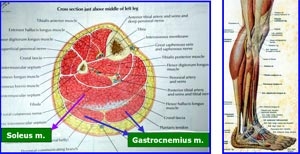

以肌肉對外觀影響最大, 考慮肌肉量(muscle volume)對外觀的影響, 以soleus(比目魚肌)和 gastrocnemius(緋腸肌)兩大肌肉群為主. Soleus m. 呈扁平半圓狀, 對小腿的功能為腳掌彎曲以及穩定腳踝, 佔體積40%, 屬於白肌(white muscle)的一種, 幫助穩定與維持作用, 因此移除它, 後遺症大.

至於gastrocnemius m., 呈突起紡錘狀, 最鼓處在中段的地方, 因為起源處(origin)位於大腿股骨的condyle位置, 附著連結(insertion)至Achilles tendon, 主要為"強化輔助"其它肌肉的作用, 包括彎曲膝蓋(knee flexion), 腳內翻(adduction)等, 屬於紅肌(red muscle)的一種, 幫助快速短期移動(short-term speed)的功能, 如果不當運動健將或舞者, 拿掉它, 後遺症較小. 另外因為它的肌肉纖維呈斜向安排, 所以肌肉伸展不完全, 導致易往旁邊發展的趨勢. 西方人其實此肌肉也蠻大塊的 只因為較高大, 所以肌肉分散在長距離, 並得以延申, 伸展, 不致於激突, 所以長高一點還是不錯的(見下圖). 根據肌皮瓣轉移(muscle flap transfer)的大量重建臨床經驗, 重建顯微手術醫師才能熟悉此處的解剖學位置與術前術後結果, 而非隨便一個美容外科醫師就可以操刀, 因此台灣做此神經整形手術(nerve plasty)的人少, 並非此手術特別難.